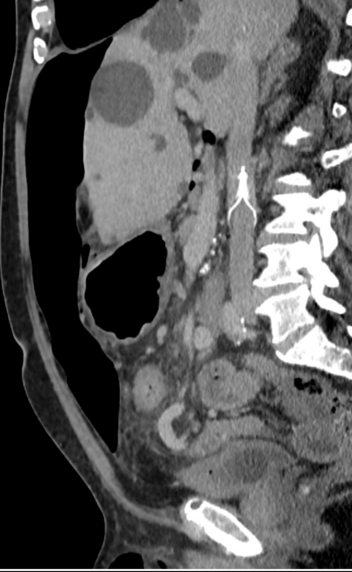

The inclusion of both mechanical and pharmacological VTE prophylaxis in our protocol is a deliberate design feature of this protocol, initially based on theoretical considerations outlined in Rosen’s Atlas of Abdominal Wall Reconstruction (1st edition, Chapter 15, page 250), which suggests that increased intraabdominal pressure from progressive insufflation may predispose patients to venous stasis and thromboembolic events [20]. This physiological rationale formed the basis of our early decision to include IVC filter insertion alongside weight- and renal-adjusted prophylactic low molecular weight heparin (LMWH), initiated at week T-5 before PPP commenced (Fig. 3).

Fig. 3

CT reformatted in the sagittal plane showing pneumoperitoneum and IVC filter